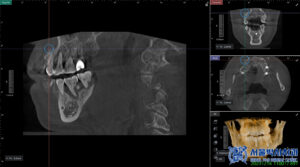

무절개 임플란트는

말 그대로 잇몸을 절개하지 않고

임플란트를 식립하는 방식으로,

컴퓨터 분석을 통해 미리 계산된

정확한 위치와 각도로 위 사진과 같은

수술 가이드를 제작하고,

가이드를 이용해 임플란트를 심기 때문에

수술 부위의 오차를 줄일 수 있습니다.

가이드는 컴퓨터 분석의 정밀한 계산을 통해

고성능 3D프린터로 제작됩니다.